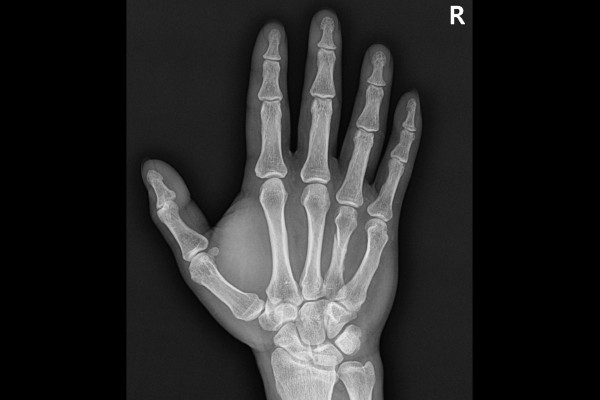

수술 후 X-RAY를 보면 휘어진 부분 없이 잘 고정된 것이 확인됩니다.

환자분께서는 별다른 문제 없이 잘 회복하셨고, 수술 후 6주가 지난 시점에서 핀을 제거하고 찍은 X-RAY 사진을 확인했을 때, 뼈가 어긋남 없이 잘 붙은 것을 확인할 수 있습니다.